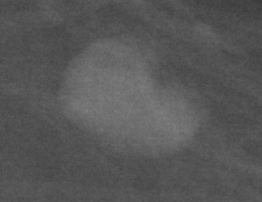

In our experiments, we use the Digital Database for Screening Mammography (DDSM) [4], a collaboratively maintained public dataset at the University of South Florida. It comprises approximately 2500 studies each containing both mediolateral oblique (MLO) and craniocaudal (CC) views of each breast. Each image is grayscale and accompanied by a mask specifying the region of the pre-segmented mass if present. Examples of benign and malignant masses are shown in Fig. 1.

Deep learning models often lack interpretability and as such are hard to adopt for practical use in medical settings. [21] describe a methodology to visualize saliency maps which show the regions of an image the network is sensitive to when making predictions. This is performed by computing the gradient of the image with respect to the unnormalized class scores. Regions with larger gradient indicate higher contribution to the prediction (brighter in Fig. 3). Both the AlexNet and GoogLeNet learn to attend to the edges of the mass, which is a high-signal criterion for diagnosis, while also paying attention to context.